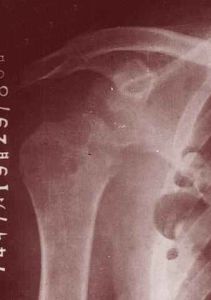

肩關節結核的肱骨頭呈現類圓形穿鑿樣改變。膝關節結核在脛骨上端關節板面兩側呈現小的穿鑿樣改變,恥骨結核在恥骨聯合或恥骨板呈現類囊狀或不規則的破壞。